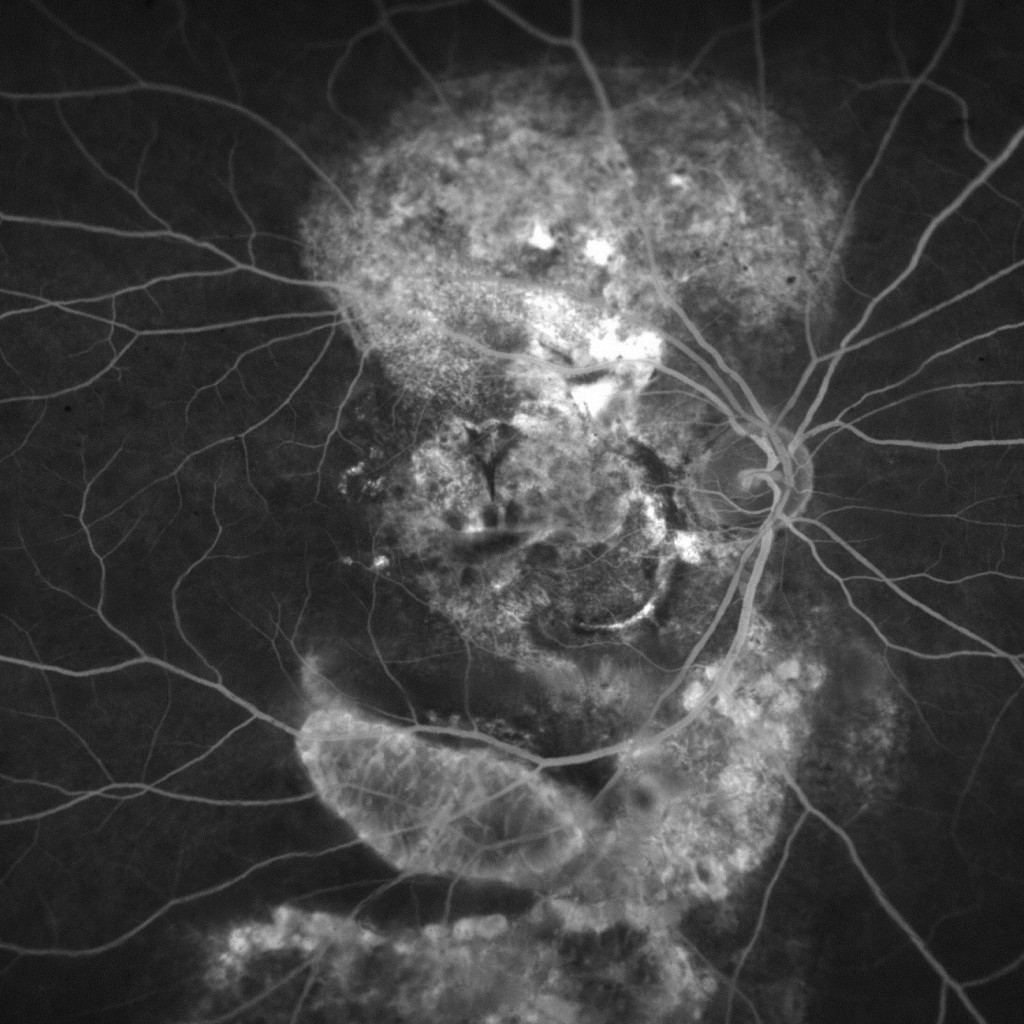

AMD_edited

Full size 1464 × 1464

Published inAMD_edited